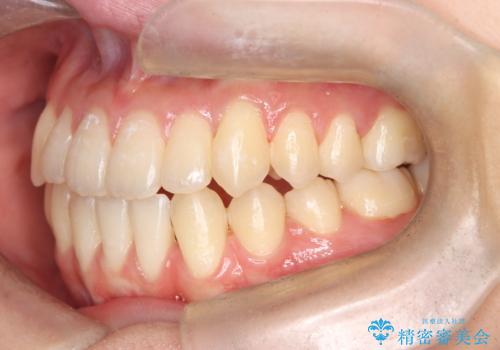

転院という不安な状況にある患者様のストレスを最小限に抑えつつ、歯の健康を最優先にした処置を行いました。

装置の変更と歯肉への配慮: ワイヤー矯正は歯の根(歯根)を平行に移動させる「歯体移動」を得意としています。本症例では、歯肉退縮を防ぐために、歯の傾きを精密にコントロールしながら抜歯スペースを閉じる必要がありました。ワイヤー装置を用いることで、インビザラインでは難しくなっていた三次元的な細かい調整を可能にしました。

リカバリーのプロセス: 適合が悪くなったインビザラインを一旦中止し、ブラケットを装着。停滞していた歯の移動を再開させ、上下の正中(中心)や奥歯の咬み合わせを一つひとつ整えていきました。